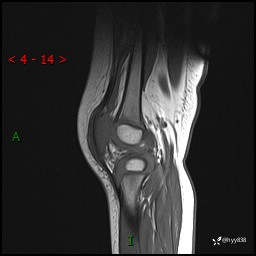

现病史:患儿1月前无明显诱因出现左下肢跛行,伴左膝关节红肿,无发热、咳嗽、恶心、呕吐等症,于当地医院就诊行X线片未提示异常,今至我院门诊就诊,门诊医师拟“跛行待查”收入院。 病后,患儿精神、食欲可,睡眠欠安,大小便通畅,体力体重无明显下降。

左膝MRI平扫